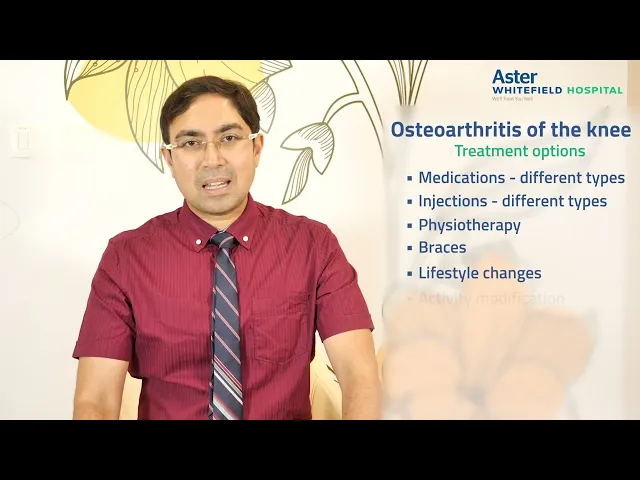

Robotic Joint Replacement & Advanced Sports Orthopedic Care

At Robotic Joints & Sports Ortho Centre, patient care is guided by precision, innovation, and experience. Dr. Kumardev Arvind Rajamanya specializes in robotic-assisted knee and hip joint replacement and sports orthopedic treatments, helping patients regain pain-free movement, mobility, and long-term function. Every treatment plan is designed with a strong focus on accurate diagnosis, advanced surgical techniques, and structured recovery support.

Advanced Orthopedic Services Focused on Robotics & Sports Care

At Robotic Joints & Sports Ortho Centre, Dr. Dr Kumardev Arvind Rajamanya offers specialized orthopedic services with a strong focus on robotic-assisted joint replacement and sports injury management. Every service is guided by precision, advanced techniques, and a patient-first approach aimed at restoring mobility, strength, and performance.

At Robotic Joints & Sports Ortho Centre, Dr. Dr Kumardev Arvind Rajamanya offers specialized orthopedic services with a strong focus on robotic-assisted joint replacement and sports injury management. Every service is guided by precision, advanced techniques, and a patient-first approach aimed at restoring mobility, strength, and performance.